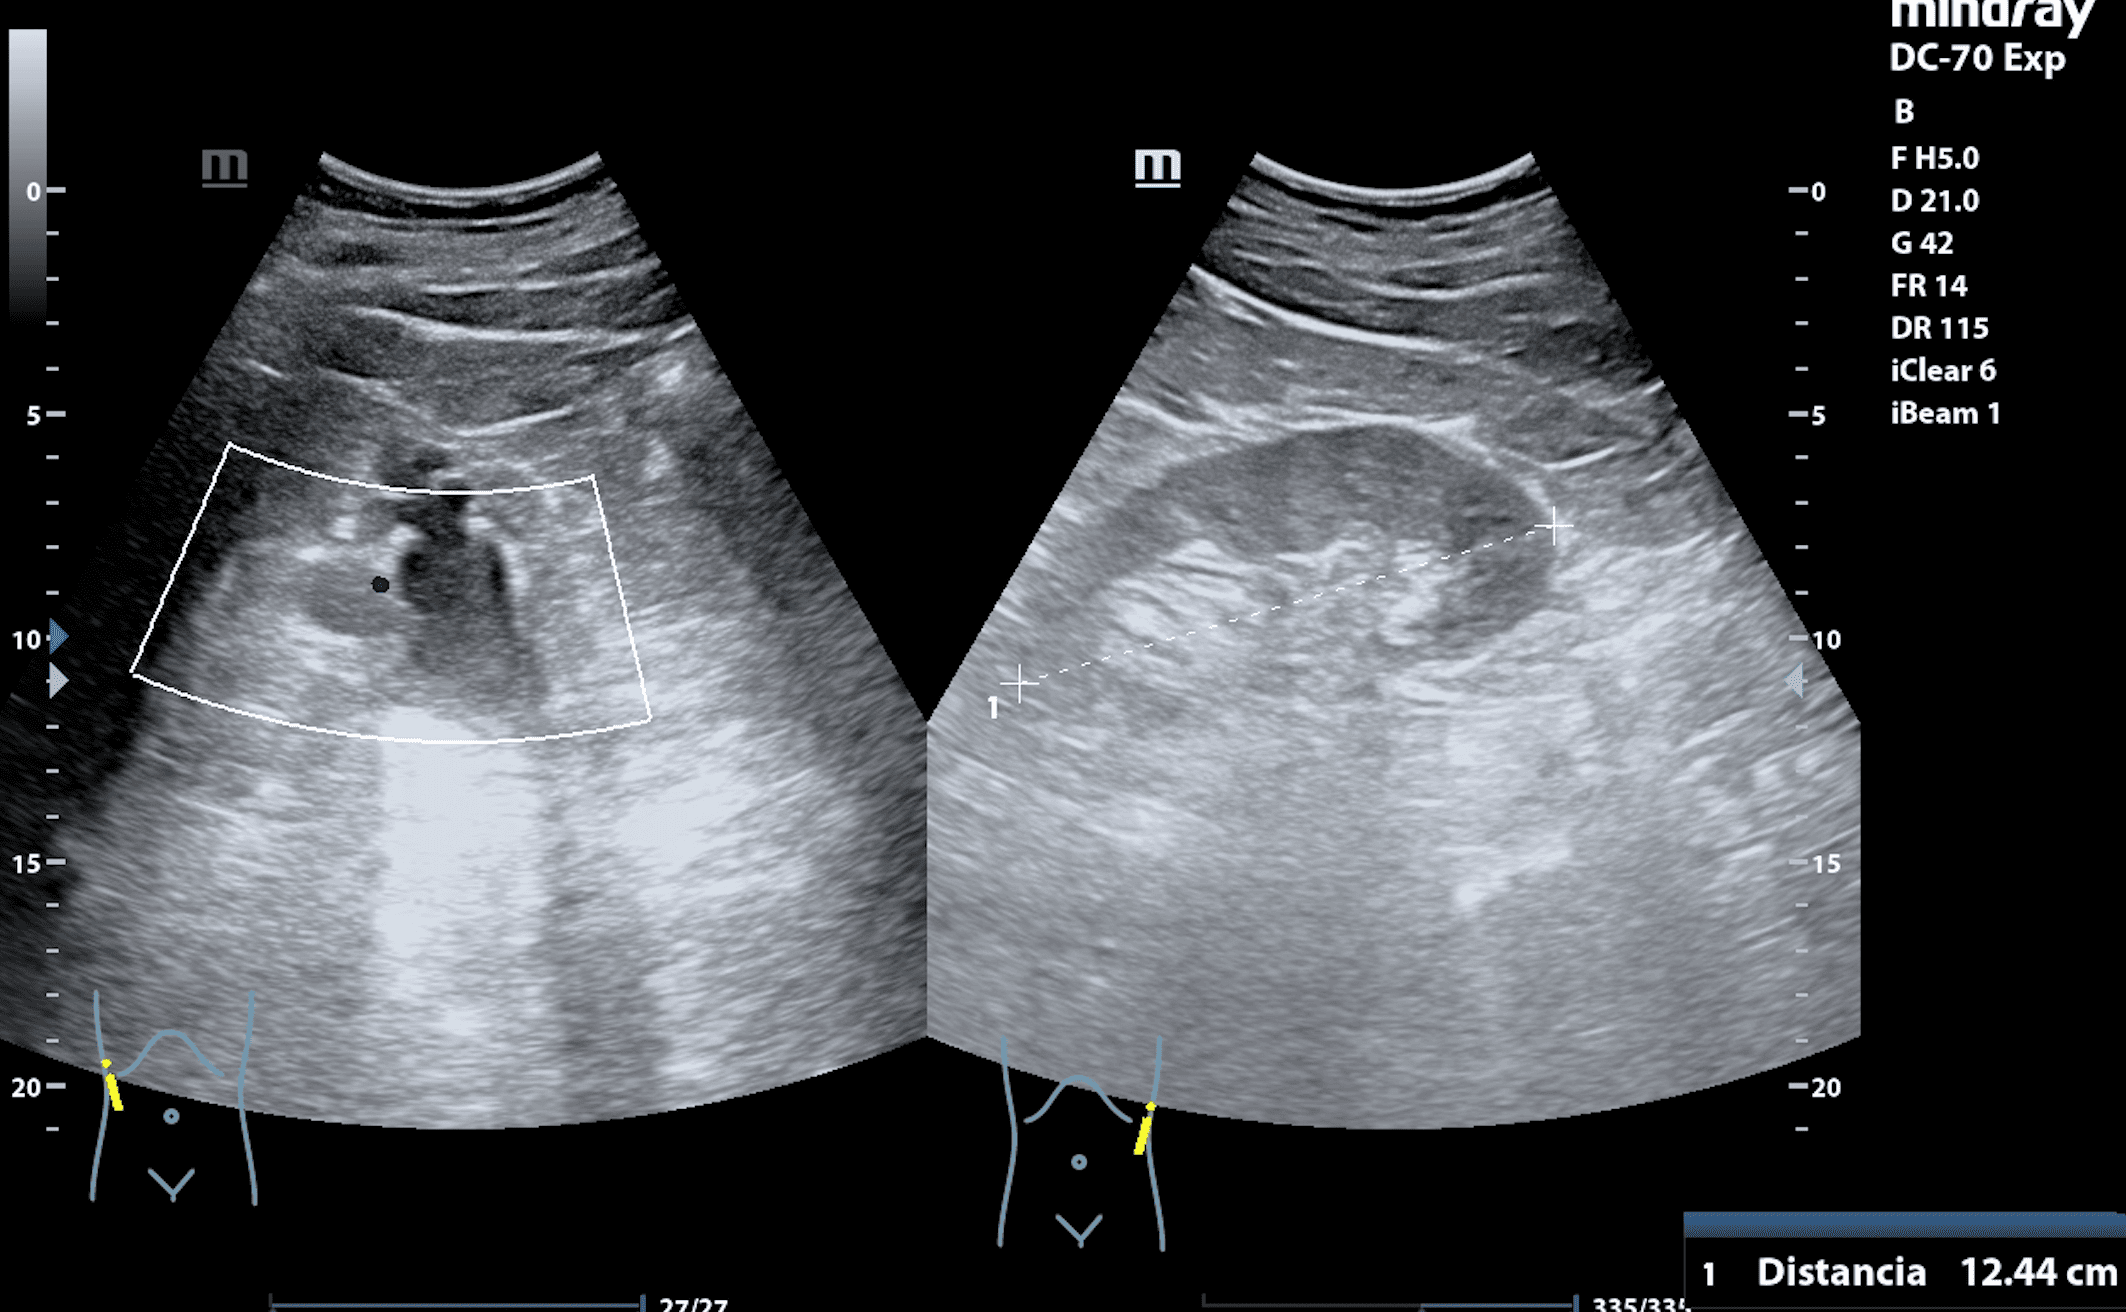

Se realiza ecografía en la misma consulta a fin de descartar cólico renal complicado.

Se observa a nivel de riñón derecho imagen anecogénica en seno renal, con afectación de cálices y desestructuración de la cortical renal. Riñón izquierdo sin hallazgos patológicos. Jets ureterales sin alteraciones. Impresiona de hidronefrosis grado IV.

En urgencias se realiza analítica con valores dentro del límite de la normalidad. Se descarta alteración de la función renal. Se confirman los hallazgos mediante ecografía en servicio de urgencias hospitalario.